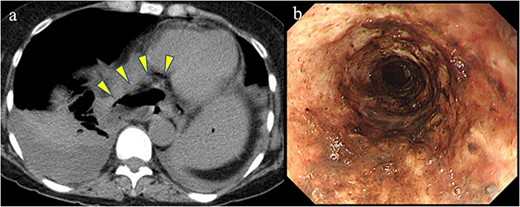

A 58-year-old woman with severe stricture of the lower esophagus was referred to our institution. She had been receiving medication to treat GERD at multiple facilities for the past 5 years. Six months prior to the referral, she underwent laparoscopic esophageal repair for esophageal rupture (Fig. 1a). After the rupture, she eventually presented with NE (Fig. 1b), a condition that consequently led to severe stenosis of the lower esophagus (Fig. 2). Multiple biopsies did not confirm any malignancy in the esophagus, and endoscopic balloon dilatation temporarily enabled endoscopic observation of the gastro-duodenum, which had no significant abnormal findings, but failed to relieve the constriction. Computed tomography revealed a 10-mm hypervascular mass on the anterior wall of the duodenum, suggestive of a gastrointestinal stromal tumor (Fig. 3); there were no findings suggestive of esophageal malignancy. Pathological diagnosis of the duodenal mass could not be determined because the endoscope used for endoscopic ultrasound-fine needle aspiration could not pass through the esophageal stricture.

Previous conditions of the esophagus. Esophageal rupture accompanied by a massive mediastinal abscess (arrowheads). Necrotizing esophagitis of the lower esophagus.